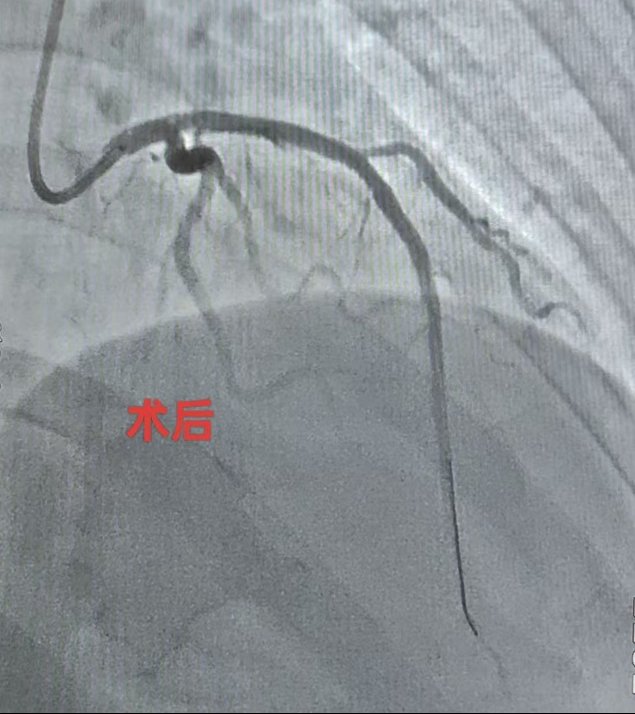

(术前术后冠状动脉对照)

听说要做心脏手术,王女生十分紧张,“总感觉自己得了大病”。魏望江便亲自前去劝解。为了让患者安心,同时确保第一例心脏介入手术顺利开展,魏望江特意邀请北京地坛医院心内科副主任(主持工作)管浩等人讨论病情,在管浩主任的指导下,根据患者情况制定合理的手术和治疗方案。4月16日,由北京地坛医院董茜、郑迪两位专家主刀,徐州医院导管室医护人员参与,为王女士行心脏冠状动脉造影及支架置入术。术后患者恢复良好,无并发症,各项检查指标均在合理范围,即将办理出院。